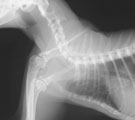

初診時頸胸部X線所見。頚部気管狭小化が認められた。 気管支鏡所見。喉頭直下の狭窄。全周性粘膜肥厚、凹凸不整あり。 粘膜肥厚部の病理組織所見。間質に軽度の線維化を伴ったリンパ球主体の炎症細胞浸潤あり。 Tチューブ設置後頸胸部X線所見。気管開存し、努力呼吸が消失した。

経過:受診時、T:37.4℃、P:138/分、R: 28。著しい吸気努力。吸気時に頚部気管中央部に強い高音調喘鳴音あり。頚部触診にてマス病変なし。SpO2<90%。血液ガス分析にてpHa 7.34, Paco2 56 mmHg, Pao2 64 mmHg, [HCO3-] 29.4 mmol/L, A-aDo2 19 mmHgと、重度な肺胞低換気所見を示した。肺機能には異常なく、中枢気道閉塞によると考えられ、気道開存処置で症状改善することが見込まれた。ただちに酸素室管理とした。同日、気管支鏡検査にて喉頭直下に全周性粘膜肥厚と粘膜表面の凹凸不整がみられた。最狭窄部を気管切開後、外径6mmのTチューブを設置した。術後、呼吸困難は消失した。気管支鏡下粘膜生検にて、間質に軽度の線維化を伴ったリンパ球主体の炎症細胞浸潤の病理組織所見が得られた。生検標本洗浄液の培養にて菌は検出されなかった。気道ステント処置に加え、ネブライゼーション(ステロイド、エピネフリン、抗生剤)およびステロイド・CPシロップ内服にて術後管理を行った。術後10日目に、血液ガス分析にてpHa 7.34, Paco2 30 mmHg, Pao2 95 mmHg, [HCO3-] 15.8 mmol/L, A-aDo2 18 mmHgと、肺胞低換気所見は消失し、正常化したので、退院とし自宅管理となった。2ヶ月後に、気管支鏡検査で内部観察後、可能であればTチューブを抜去を試みることになった。